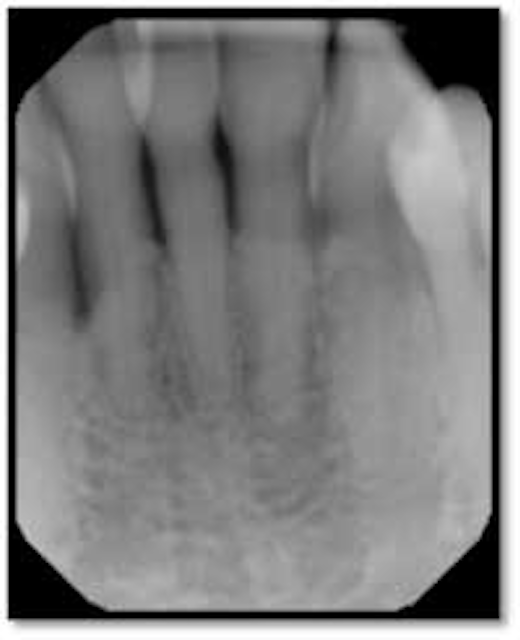

Case study use of perioscopy and LANAP for treatment of moderate Which Is Not True Of Perioscopy Combined with ultrasonic instruments, endoscopic debridement can be accomplished in a minimally invasive manner. Periodontal disease generally is not triggered by which of the following factors? Which is not true of perioscopy ? It is associated with the ducts of the major salivary glands. It is a new procedure that uses a miniature dental endoscope with video , lighting ,. Which Is Not True Of Perioscopy.

3 Ultrasonic Endoscopic Periodontal Debridement Pocket Dentistry Which Is Not True Of Perioscopy Which is not true of perioscopy? Of the following are the two basic forms. Periodontal disease generally is not triggered by which of the following factors? It is unable to identify initial decay or cracks. Which is not true of perioscopy? Which is not true of perioscopy ? It is associated with the ducts of the major salivary glands. What. Which Is Not True Of Perioscopy.

The Perioscopy System, Part 4 Case studies by Robert Gottlieb, DDS Which Is Not True Of Perioscopy What is not true of subgingival calculus? It is a new procedure that uses a miniature dental endoscope with video , lighting , and magnification. Which of the following systemic conditions is not associated. Which is not true of perioscopy ? Periodontal disease generally is not triggered by which of the following factors? Of the following are the two basic. Which Is Not True Of Perioscopy.